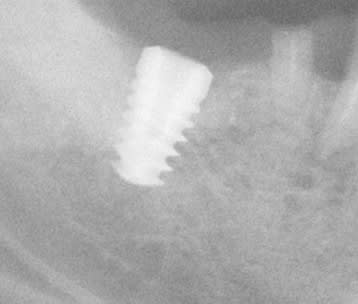

J'ai besoin de votre aide pour identifier cet implant posé il y a 4 ans dans une autre ville avant que le patient ne déménage et "oublie" de prendre soins de lui.

En fait la seule radio qui serait exploitable est la première…..mais comme elle est floue, je perds plein d’info….

Ce que j’ai trouvé de plus proche pour l’instant c’est l’implant conique de GC…..mais rien de certain….

Bon, j'ai revu le patient afin de virer 46 et j'ai enfin réussi à faire une meilleure radio, visiblement, il est bien déporté en lingual cet implant

vu ce que tu me dis sur la position très linguale....amha tu auras meilleur compte de le virer (surtout qu'il a déjà commencé de cratériser au col) et d'en poser un autre....